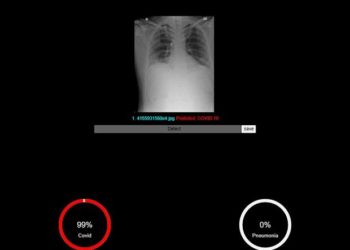

To combat covid fatalities involving the lungs, the Defence Research and Development Organisation’s (DRDO’s) Centre for Artificial Intelligence and Robotics (CAIR), with ...